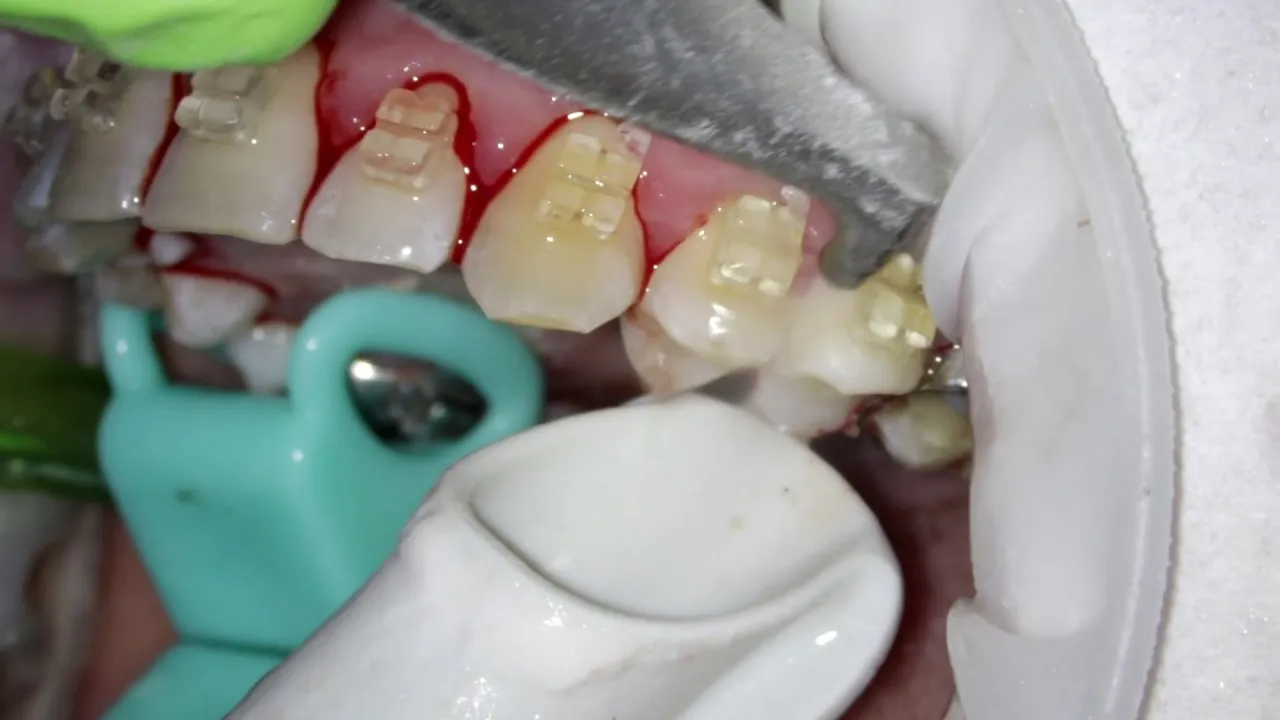

Skaling i piaskowanie: jak wygląda podstawowy zabieg higienizacji?

Podstawą profesjonalnego leczenia zapalenia dziąseł jest kompleksowa higienizacja, która zazwyczaj obejmuje dwa kluczowe zabiegi:

- Skaling: To procedura polegająca na usunięciu kamienia nazębnego, zarówno naddziąsłowego, jak i poddziąsłowego, za pomocą ultradźwięków. Specjalistyczne urządzenie, tzw. skaler, generuje drgania o wysokiej częstotliwości, które skutecznie rozbijają twarde złogi kamienia, nie uszkadzając przy tym szkliwa. Jest to zabieg zazwyczaj bezbolesny, choć u osób z wrażliwymi zębami może być odczuwalny lekki dyskomfort.

- Piaskowanie: Po usunięciu kamienia, przechodzimy do piaskowania. Ten zabieg ma na celu usunięcie osadów i przebarwień z powierzchni zębów, które często powstają od kawy, herbaty czy papierosów. Wykonuje się go za pomocą specjalnego urządzenia, które pod ciśnieniem rozpyla strumień wody, powietrza i drobnego proszku (tzw. piasku stomatologicznego). Piaskowanie wygładza powierzchnię zębów, co utrudnia ponowne przyleganie płytki bakteryjnej.

Po tych zabiegach często wykonuję jeszcze polishing (polerowanie zębów) oraz fluoryzację, która wzmacnia szkliwo i zmniejsza jego wrażliwość.